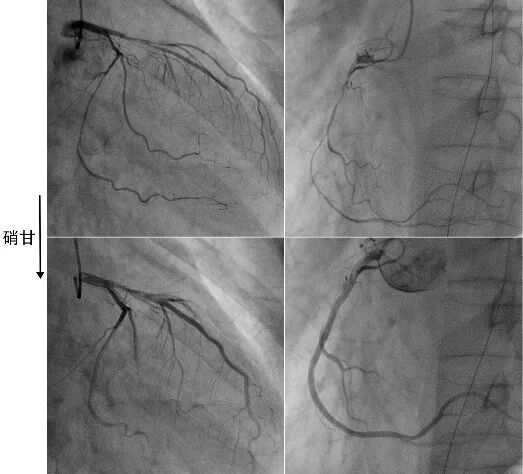

6、器械诱发狭窄

导管、导丝、球囊、或支架等器械操作可以诱发冠脉痉挛(图9-12),这不是问题。问题是,能否凭借器械诱发收缩来诊断“冠脉痉挛性疾病”(变异性心绞痛)?

一方面,若器械操作能轻易诱发痉挛,说明患者的冠脉系统属于“高敏”易激惹状态,极有可能患者症状或血管狭窄是“冠脉痉挛”所致。此时,要积极考虑“冠脉痉挛性疾病”的诊断。譬如,支架植入后诱发两端弥漫性严重痉挛,要反思原先狭窄是否也是痉挛所致?同理,延伸一下知识点,凡是器械能轻易诱发的壁内血肿,可能血管本身就具有自发性壁内血肿的潜能。

另一方面,血管收缩其实是血管的一种生理性反应而已,只要刺激足够强(物理/化学/生化),任何血管均能诱发出收缩!而“冠脉痉挛”术语专指过度敏感的、高度激惹的血管收缩。有些器械刺激比较强烈,可导致难治性、持久性的血管收缩,甚至硝酸甘油难以缓解,甚至需要间隔一段时间行CCTA或复查造影加以证实或排除。对于此类器械强烈刺激导致的痉挛,并不代表自发性痉挛,不能据此临床诊断“冠脉痉挛”或“变异性心绞痛”,不一定需要日常抗痉挛治疗。

图9 导丝诱发冠脉痉挛。

前降支中段肌桥段可疑狭窄(A),拟行IVUS检查。导丝通过后肌桥段痉挛(B),注射硝酸甘油后缓解(C)。

图10 IVUS导管诱发冠脉痉挛。

前降支中段肌桥段可疑狭窄(A),行IVUS检查后肌桥段痉挛(B),注射硝酸甘油后缓解(C)。

图11 球囊诱发冠脉痉挛。

右冠弥漫性病变,远段最重狭窄95%(A),药物球囊处理后弥漫性变细(B),注射硝酸甘油后缓解(C)。

图12 导管深插诱发顽固性痉挛。

JR4造影导管深插至右冠(A),退至开口造影提示近段严重狭窄(B),冠脉内注射硝酸甘油200μg×3次只有部分缓解(C),继续推注200μg×2次后基本缓解(D)。说明部分患者强刺激后痉挛比较持久。该病人并无血管痉挛的临床表现,术后不需要抗痉挛治疗。